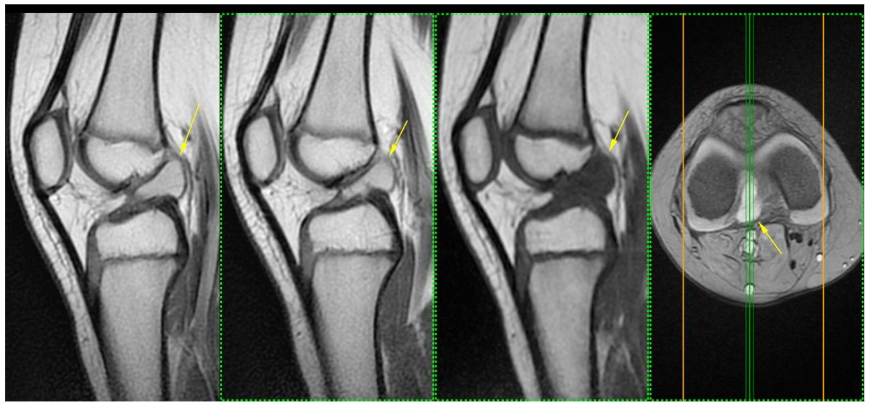

MRI of the right knee demonstrated an intrasubstance ganglion within the ACL occupying the proximal and middle thirds (Figure 1), associated with features suggestive of a near-complete tear, predominantly affecting the posterolateral bundle.

Simple MRI of the right knee. Yellow date ganglion